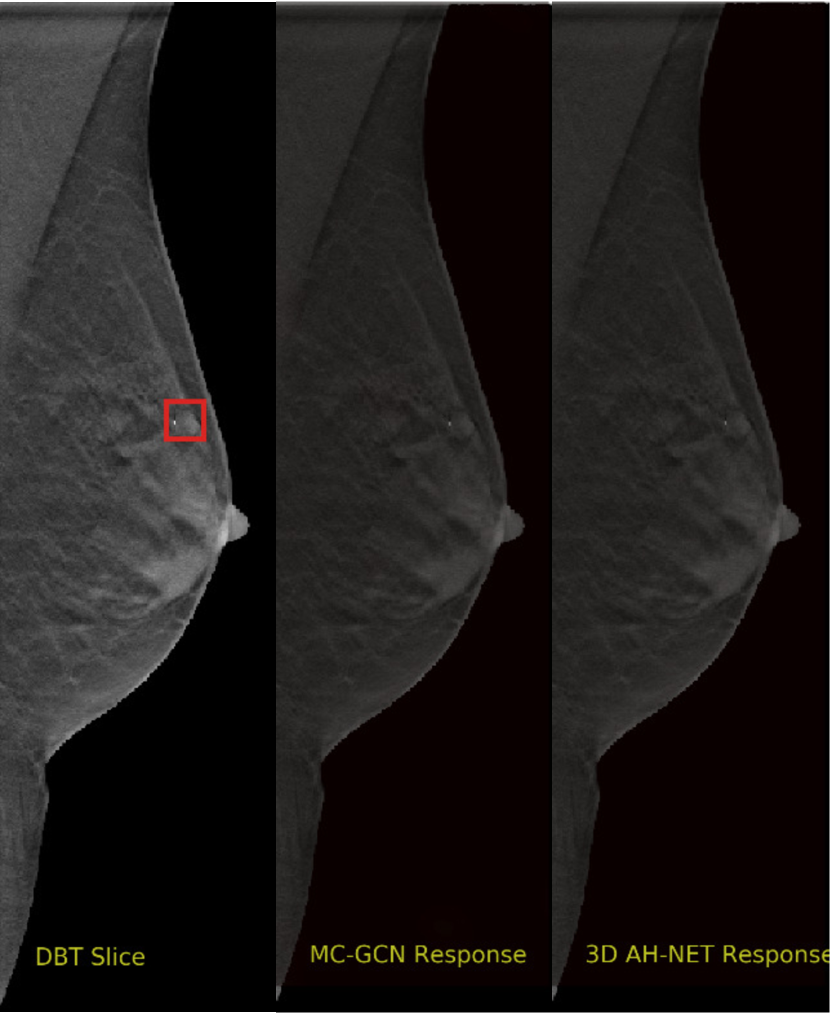

We selected some example slices from the DBT dataset to demonstrate the advantage of our proposed AH-Net for the Breast cancer screening. From Fig. 8 to Fig. 12, we show slices from five test DBT volumes that both the MC-GCN and the proposed 3D AH-Net could successfully detect the suspected breast lesion. The original DBT slice is shown on the left with the lesion annotated by our radiologist. Please note the original annotation is a 3D box. The figures in the middle and on the right are response maps from MC-GCN and 3D AH-Net overlaid on the original image, respectively. The detection locations obtained with non-maximal suppression are displayed with cross markers. As shown in the images, the proposed network can detect breast lesions varying in sizes and appearances. The confidence of the 3D AH-Net is usually higher than that of MC-GCN. From Fig. 13 to Fig. 17, we show five volumes that MC-GCN failed to detect the lesions since the lesions were not distinguishable from other breast tissues using the information within the slice. In contrast, 3D AH-Net was able to detect the lesions from such volumes using the 3D context between slices. As shown in Fig. 18 to Fig. 22, there are also volumes with lesions that both network failed to detect. Such lesions normally reside in the dense breast tissues. The boundary between these lesions and the normal breast tissues usually have low contrast. The networks sometimes also confuse them with other roundish structures in the breast such as lymph nodes or skin moles.

Refer to caption

Figure 16: Example DBT slice 9 with a lesion that can only be detected by 3D AH-Net. The lesion is highly blended within the dense breast tissues which makes it challenging for both the radiologists and the networks to detect with only a 2D view of the structure. The lesion can be detected by considering the consistency of the structure across a few neighbouring slices.

Figure 17: Example DBT slice 10 with a lesion that can only be detected by 3D AH-Net. The lesion is highly blended within the dense breast tissues which makes it challenging for both the radiologists and the networks to detect through a slice 2D slice. The lesion can be detected by considering the consistency of the structure across a few neighbouring slices.